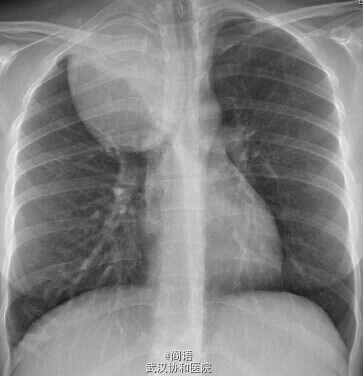

患者,女,28岁,体检时胸片发现右肺上顶部巨大肿块。否认呼吸道症状。追问病史,剧烈运动后面部有不对称性潮红,右脸易多汗。

MRI扫描提示神经鞘瘤。

胸外科进行切除,组织学证实为神经鞘瘤。